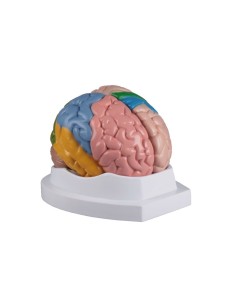

Des modèles anatomiques détaillés pour tous les besoins

Du crâne en 22 parties à verrouillage magnétique aux modèles de colonne vertébrale, des modèles d'articulation aux modèles de cœur, chaque pièce de notre collection est conçue pour une immersion totale dans l'étude de l'anatomie humaine. Nos modèles, réalisés à partir de scans d'os réels, garantissent une expérience tactile authentique et une fidélité de poids presque identique aux originaux.

Indispensables aux étudiants comme aux professionnels, nos modèles anatomiques sont des outils pédagogiques qui permettent d'observer les structures anatomiques avec précision, en évitant les dissections ou les études invasives. Ils sont également utiles pour expliquer les pathologies aux patients, ce qui rend la communication plus efficace et permet de gagner un temps précieux.